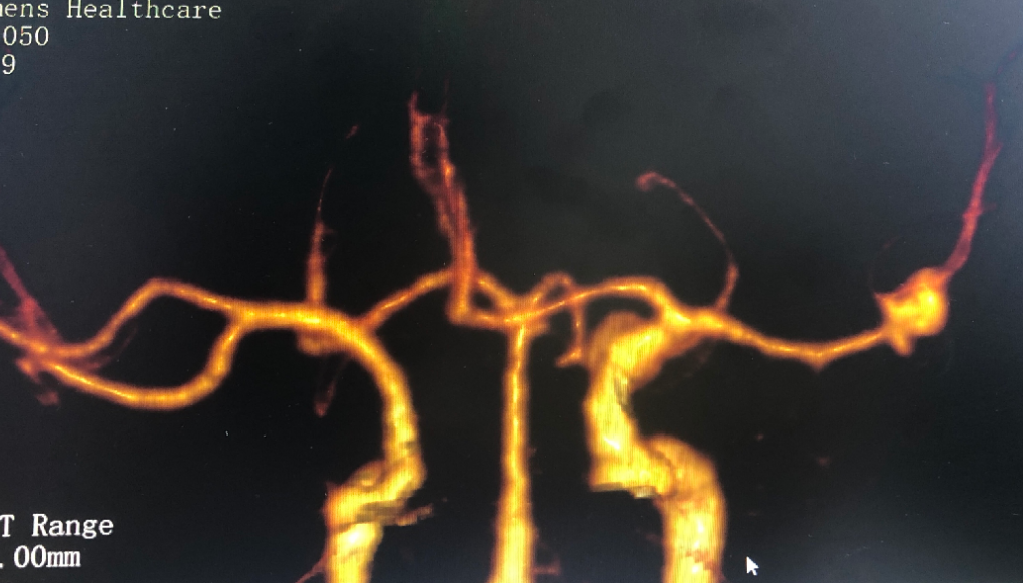

到院后,神經(jīng)外科醫(yī)生仔細(xì)查體并安排相關(guān)檢查,經(jīng)過(guò)CT檢查顯示,她的腦袋里竟然長(zhǎng)了兩個(gè)“瘤”:左側(cè)頸內(nèi)動(dòng)脈C6段、大腦中動(dòng)脈M1段動(dòng)脈瘤,更為嚴(yán)重的是,動(dòng)脈瘤已經(jīng)破裂,導(dǎo)致蛛網(wǎng)膜下腔出血!

△患者檢查影像